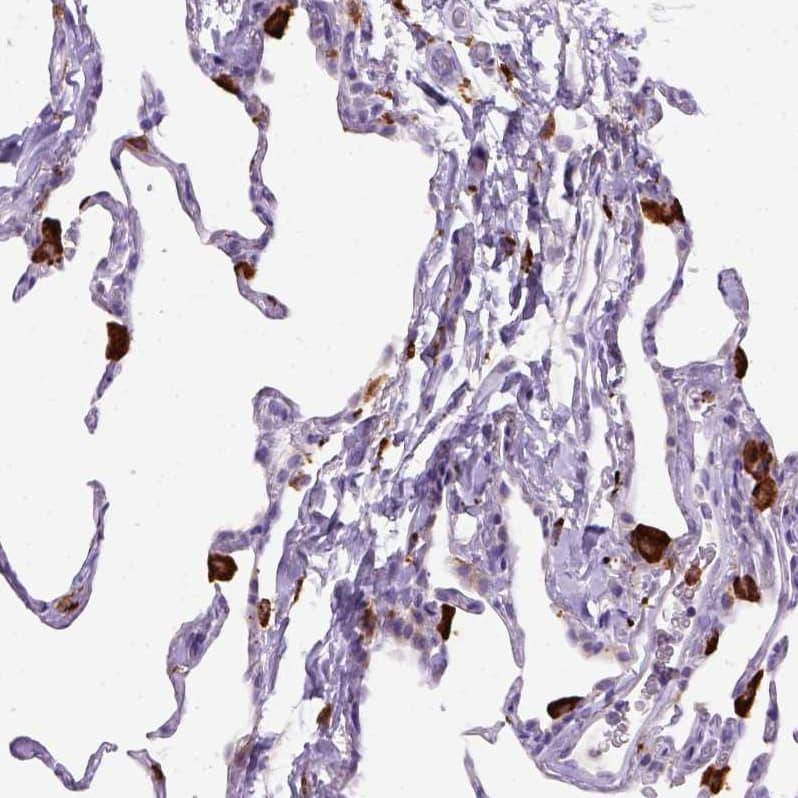

Staining of human lung shows strong cytoplasmic positivity in macrophages.